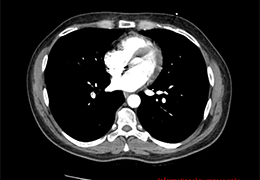

成像智能。

Eclipse 成像智能功能提供强大的处理能力和最佳质量的影像,同时减少质量错误并提高剂量效率。

凭借 AI、专有算法和先进的影像处理能力,提供出色的影像质量和无与伦比的诊断信心。

与标准影像处理相比,智能降噪功能可使客户降低辐射剂量,而不会损失影像质量。这在新生儿和儿科成像中尤其重要,在这种情况下以尽可能低的剂量成像至关重要。